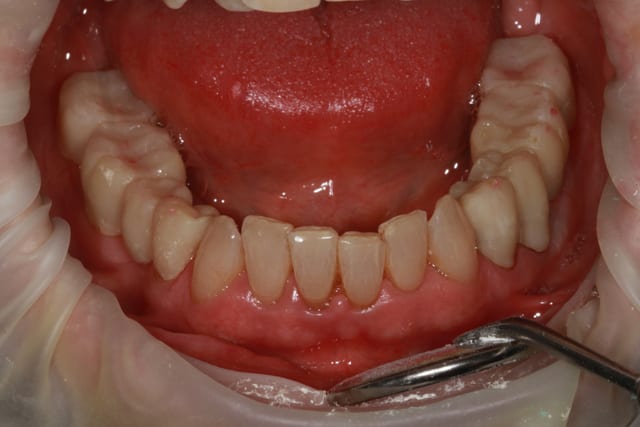

patiente 62 ans région Parisienne, appelle pour un avis, son praticien, paro, imlpanto etc... lui dit que sa paro n'a plus besoin de soin et propose pour les 6 antérieurs (j'ai le devis sous les yeux) 6 Inlay Core et 6 CCM...

Les panos sont du départ, les photos sont après un nettoyage ...profond et soins.

donc dans un premier temps détartrage, détartrage, détartrage Wax up, ....surfaçage couronne , amalgame à la benne taille des postérieurs inférieure et pose de provisoires pour valider la nouvelle DV.